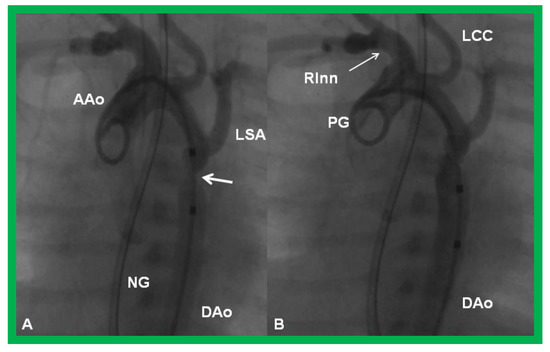

Figure 23.

Cineangiographic frames from aortic arch angiograms in a 20° left anterior oblique views, illustrating a narrowed (coarcted) aortic segment (arrow) priot to balloon angioplasty (A) which improved following balloon angioplasty (B). Note mild hypoplasia of the distal transverse aortic arch and isthmus. AAo, ascending aorta; DAo, descending aorta; LCC, left common carotid artery; LSA, left subclavian artery; NG, nasogastric tube; PG, pigtail catheter; RInn. right innominate artery. Modified from Reference [90].